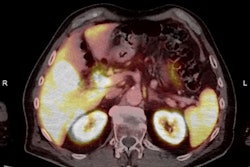

Over the past three years, clinical staff at Dublin’s Mater Misericordiae University Hospital have built up considerable expertise in F-18-PSMA-1007 PET/CT imaging, especially for prostate cancer. A multidisciplinary team from the Mater presented its findings and cases at ECR 2025 and has agreed to let us publish some of its images.